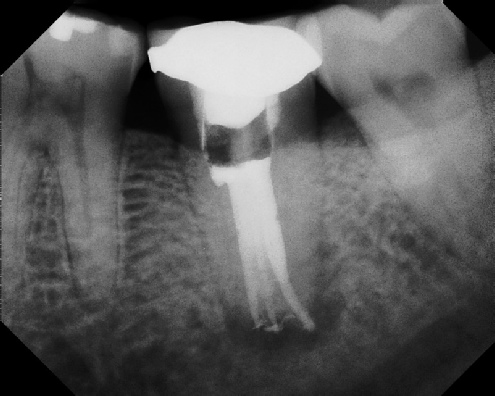

Root Canal Retreatment - Meriden 8 mos. recall Post-op Pre-op